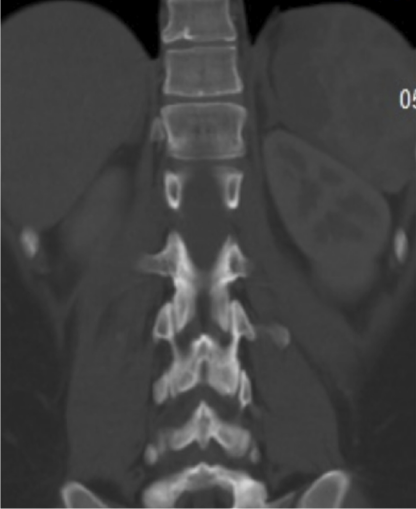

Se realiza tomografía computada (TC) de abdomen (doble contraste) con los hallazgos de infarto esplénico del polo superior (15% aproximadamente), mínimo derrame pleural izquierdo, y tubo gástrico indemne, sin evidencia de fugas ni colecciones intra-abdominales (Figuras 1-2).

Figura 2. Infarto esplénico